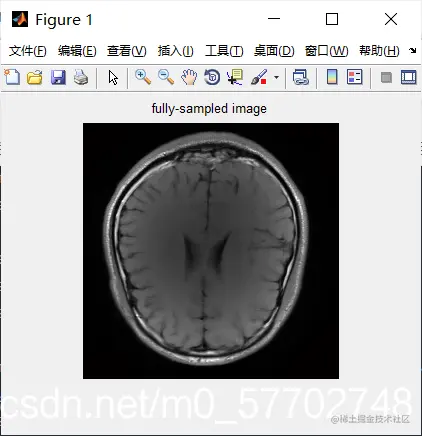

tic;im1_Rec=solver_ADMC(y1,mask1,paramSIDWT);time_SIDWT_CS1=toc % solve the L1 norm minimization problem with ADMC

Evaluation_ana = Evaluation_CS_MRI(im1,im1_Rec)

figure,imshow(abs(im1_Rec));title('Reconstructed image')